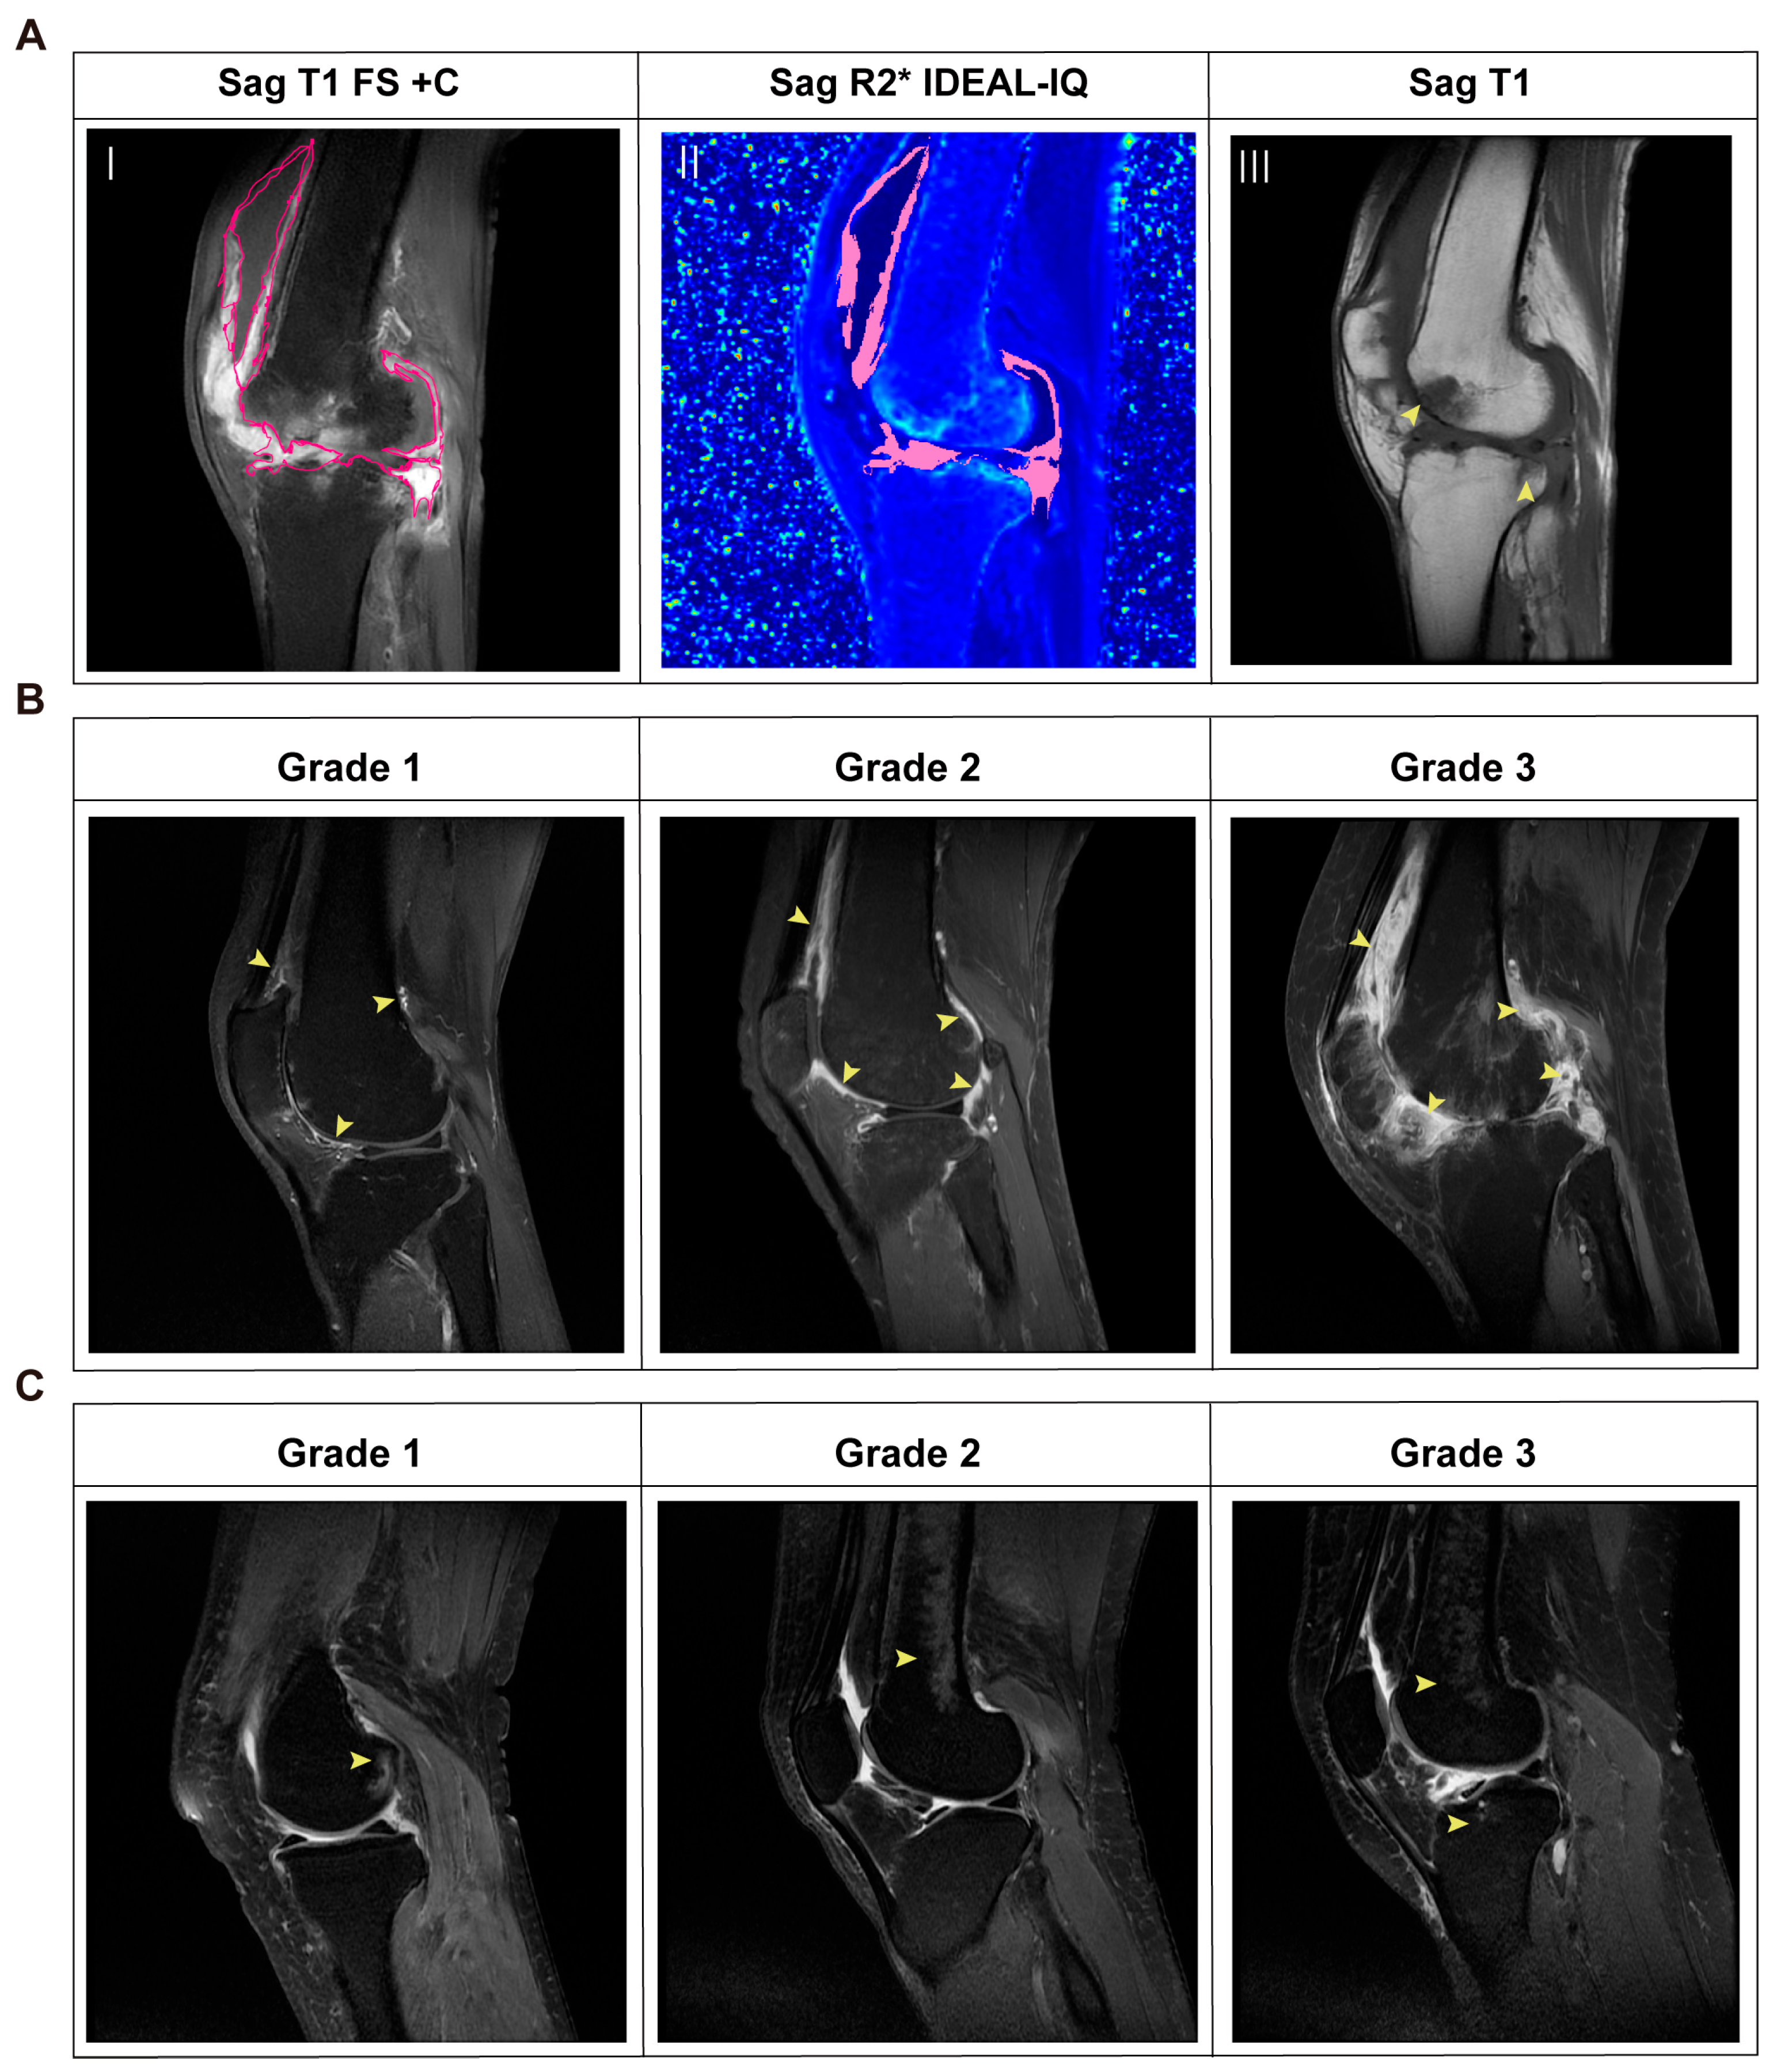

3.2. Quantitative MRI Assessment in RA Patients

3.3. MRI R2* Is a Practical Method to Quantify Iron Accumulation in RA Joints

3.4. Iron Overload in RA Joint Lesions Correlates with Structural Injury